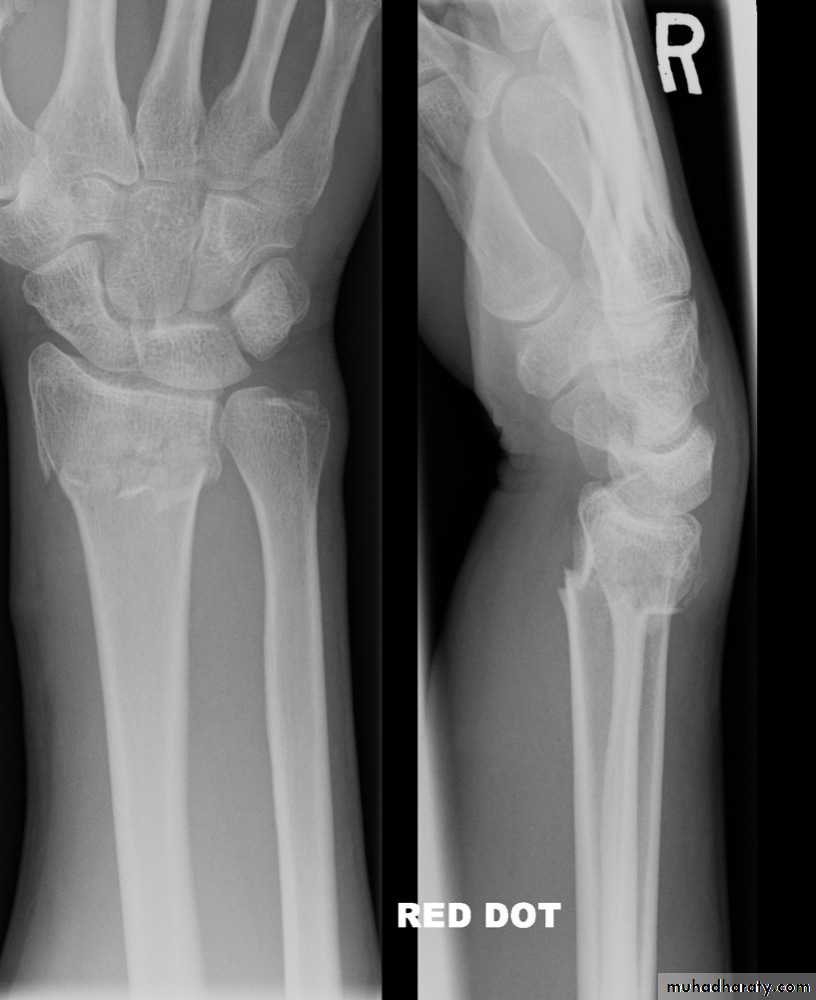

Dr. Saad Abdul AzizColle’s fracture

is a transverse fracture of the distal radius just above the wrist with dorsal displacement of the distal fragment.It’s the most common of all fractures in older people.

fall on outstretched hand, its either undisplaced or displaced .In displaced fracture the distal fragment collapses into extension, dorsal displacement, radial tilt and shortening.

X-rays: AP&Lat. Views